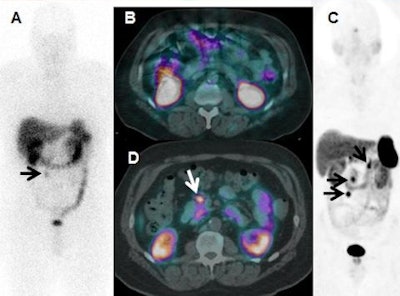

The study compared both imaging methods on 78 of 97 consecutively enrolled patients with known or suspected pulmonary or gastroenteropancreatic neuroendocrine tumors. The researchers found that Ga-68 DOTATATE PET/CT combined with CT and/or liver MRI changed care in 28 (36%) of the 78 patients (JNM, May 2016, Vol. 57:5, pp. 708-714).

Ga-68 DOTATATE PET/CT also correctly identified three patients for peptide receptor radiotherapy who had been incorrectly classified by In-111 pentetreotide.